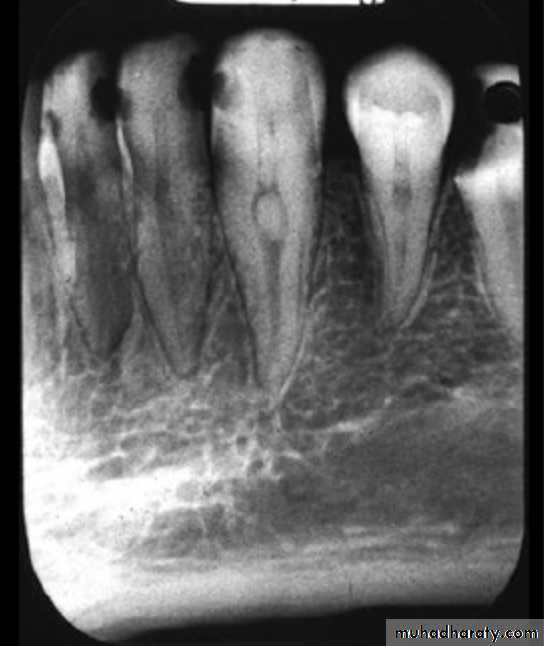

It is that portion of pulp preparation which extends from canal orifice to the apical foramen. The shape of root canal varies with size, shape, number of the roots in different teeth.The apical foramen is an aperture at or near the apex of a root through which nerves and blood vessels of the pulp enter or leave the pulp cavity.

The apical foramen is the opening from the pulp at the apex of the tooth.Accessory canals or lateral canal, extra canal located on the lateral portions of the root.